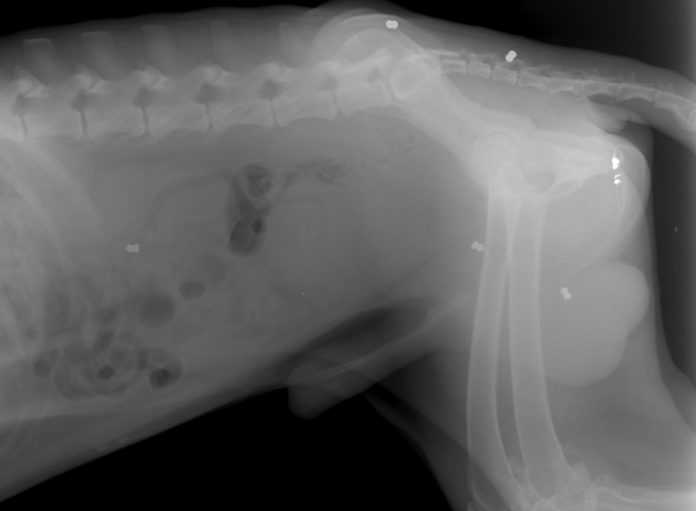

Βολές από αεροβόλο όπλο δέχτηκε στα Τρίκαλα ο Ρόντ, ο «φύλακας» σκύλος της κεντρικής πλατείας της πόλης! Η ακτινογραφία αποκαλύπτει τα σκάγια στο σώμα του ζώου.

Όπως καταγράφει το trikalavoice.gr στις ακτινογραφίες που υπεβλήθη φάνηκε να φέρει ακόμη τα σκάγια τα οποία δέχθηκε, στο σώμα του (οι εφτά άσπρες κουκκίδες).